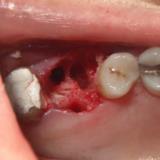

Immediate Implant Placement

A molar either maxillary or mandible always represents a little difficult and tricky scenario for implant placement immediately after extarction. There is always some sacrifice for the location, angle etc. however you save some time and patients go through a procedure once and it is a reliable method of replacing a tooth, when feasible. Dental implant is always a compromised replacement and a tooth restored with immediate placement is not any different.